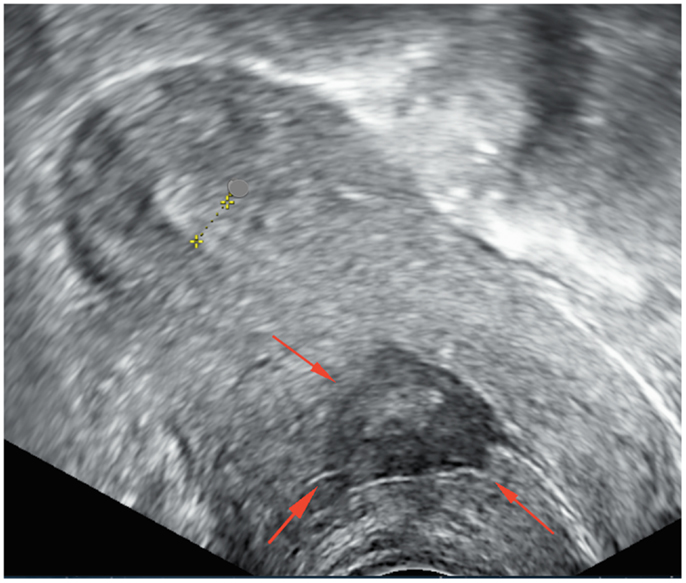

КТ диагностика тубоовариального абсцесса: Подходы и изображения

Раздел: Объективный взгляд